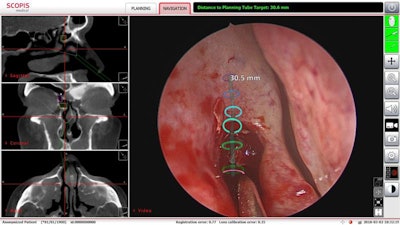

UTHealth sinus surgeons affiliated with Memorial Hermann-TMC have used augmented reality technology to perform minimally invasive sinus surgery. Image courtesy of Dr. Martin Citardi of UTHealth.The surgeons used Scopis TGS target-guided surgery technology, which allows for surgical planning from preoperative imaging studies. This planning is overlaid onto the surgeon's endoscopic view of the surgical area, assisting the surgeon in following the defined pathway and avoiding critical structures, according to Memorial Hermann-TMC.

"By using this technology, we were able to plan a pathway to drain that blocked frontal sinus and avoid the need for a more extensive procedure," Citardi said in a statement.